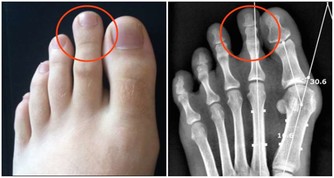

草酸:草酸會跟鈣結合形成不溶性的沉澱,即草酸鈣,多吃還會引起結石;

碳酸:碳酸飲料,如蘇打水,可樂等,攝入過多會影響體內鈣磷代謝的平衡,對骨骼生長有副作用。